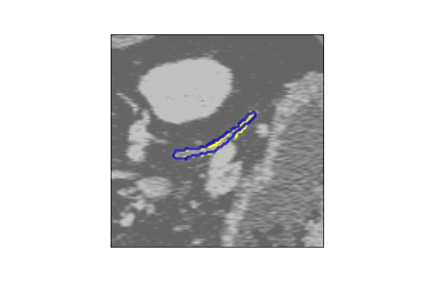

The human annotations are imperfect, especially when produced by junior practitioners. Multi-expert consensus is usually regarded as golden standard, while this annotation protocol is too expensive to implement in many real-world projects. In this study, we propose a method to refine human annotation, named Neural Annotation Refinement (NeAR). It is based on a learnable implicit function, which decodes a latent vector into represented shape. By integrating the appearance as an input of implicit functions, the appearance-aware NeAR fixes the annotation artefacts. Our method is demonstrated on the application of adrenal gland analysis. We first show that the NeAR can repair distorted golden standards on a public adrenal gland segmentation dataset. Besides, we develop a new Adrenal gLand ANalysis (ALAN) dataset with the proposed NeAR, where each case consists of a 3D shape of adrenal gland and its diagnosis label (normal vs. abnormal) assigned by experts. We show that models trained on the shapes repaired by the NeAR can diagnose adrenal glands better than the original ones. The ALAN dataset will be open-source, with 1,594 shapes for adrenal gland diagnosis, which serves as a new benchmark for medical shape analysis. Code and dataset are available at https://github.com/M3DV/NeAR.